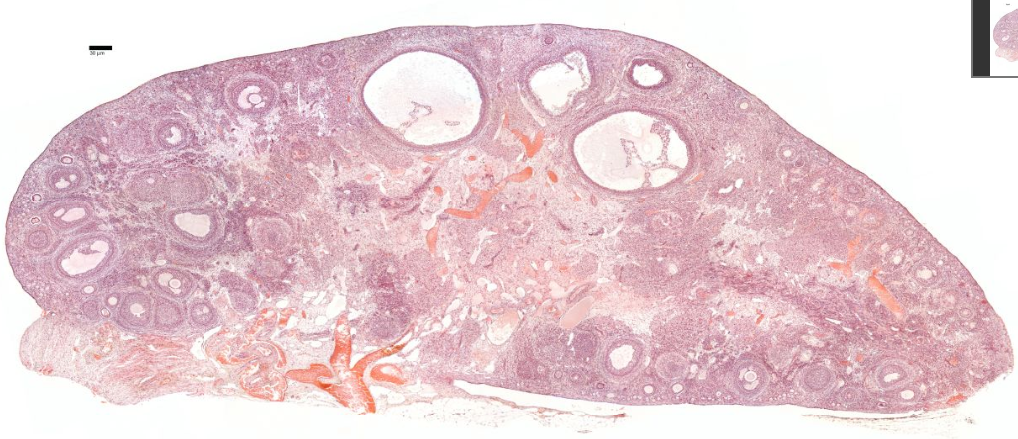

{A diagram of a sectioned ovary (a) shows the different stages of follicle maturation, ovulation, and corpus luteum formation and degeneration. All of the stages and structures shown in this diagram actually would appear at different times during the ovarian cycle and do not occur simultaneously. Follicles are arranged here for easy comparisons. The primordial follicles shown are greatly enlarged. The histologic sections identify primordial follicles (b), a primary follicle (c), a secondary follicle (d), and a large vesicular follicle (e). After ovulation, the portion of the follicle left behind forms the corpus luteum (f), which then degenerates into the corpus albicans (g). All H&E.]

Next is a cortex where the ovarian follicles can be found.

Ovarian follicles are oocytes surrounded by epithelial cells.

Included in the follicles are the cumulus oophorus, membrana granulosa, and the granulosa cells inside it, corona radiata, zona pellucida, and primary oocyte.

The zona pellucida, theca of follicle, antrum and liquor folliculi are also contained in the follicle. Also in the cortex is the corpus luteum derived from the follicles.

The most internal part of the ovary, the medulla, contains loose connective tissue and blood vessels entering the organ through the hilum from mesenteries suspending the ovary. The medulla has coiled arteries called helicrine arteries.There is no distinct border between the ovarian cortex and medulla.It can be hard to distinguish between the cortex and medulla, but follicles are usually not found in the medulla.